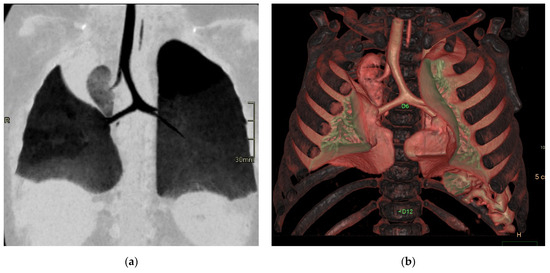

Figure 6. Hybrid congenital malformation consisting of lung seizure and CCAM. CECT MPR reconstruction (a), VR (b), and axial (c,d) images show the presence of a lobulated-margin formation located in the lower lobe of the left lung, which is consists of multiple cystic formations (diameters ranging between a few millimeters and 1.5 cm) and a consolidation zone corresponding the costodiaframmatic recess, which is supplied by a voluminous arterial branch originating from the left lateral wall of the aorta in the thoraco-thoracic passage.

In terms of location, about 85–90% of sequestrations are supradiaphragmatic, with the remaining 10–15% being subdiaphragmatic [11]. Approximately 90% of sequestrations are located on the left side. The systemic arterial supply typically comes from both the lower thoracic and upper abdominal aorta (Figure 6).